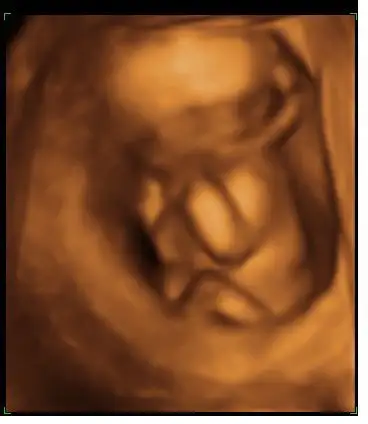

aa sanırım yaptım canım..merak edenler için..4b usg

görüntü biraz bulanık gibi ama idare edin..

oğlum,Kayra